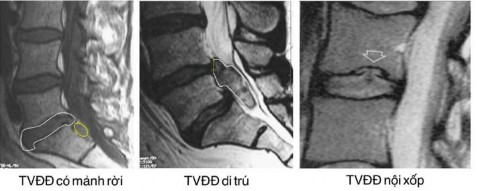

. TVĐĐ có mảnh rời: mảnh rời này thường nằm ngoài màng cứng, nhưng đôi khi xuyên qua màng cứng gây chèn ép tủy (Hình 2.2).

Hình 2.2. Hình ảnh cách xác định thoát vị đĩa đệm có mảnh rời [45].

+ Hình ảnh T2 cắt đứng dọc phát hiện được:

. Giảm tín hiệu đĩa đệm thắt lưng.

. Hình ảnh thoát vị đĩa đệm, đè ép bao rễ thần kinh và ống sống.

. Phì đại dây chằng dọc sau và phì đại dây chằng vàng từng đoạn,...